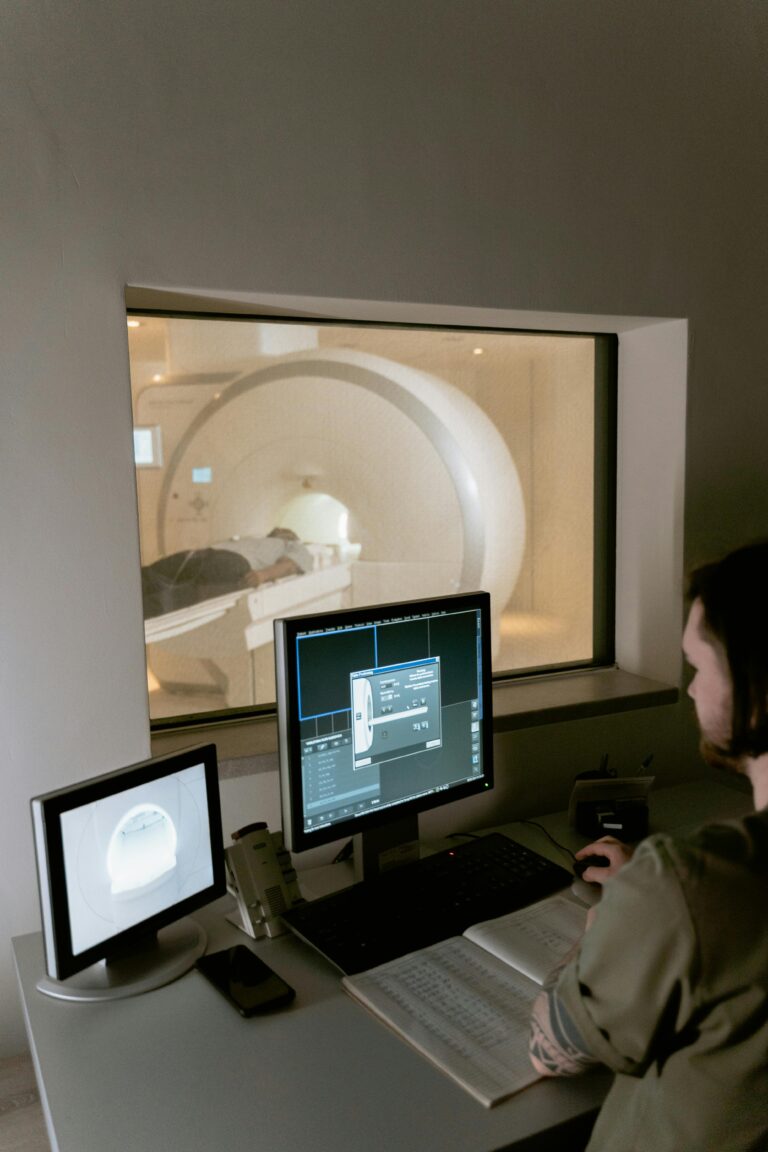

Experience high-definition imaging powered by world-class systems and specialist radiologists.

384-Slice Dual-Energy CT, 1.5T MRI & advanced radiology services for accurate, early detection.

Eurevaa Diagnostics delivers world-class radiology and imaging services powered by state-of-the-art equipment and a team of experienced specialist radiologists.

Equipped with advanced MRI, CT Scan, X-Ray, and Sonography systems, we deliver precise imaging and accurate reports you can trust. Our experienced radiologists ensure consistent quality and reliable outcomes.

Got my MRI done at Eurevaa Diagnostics and the experience was excellent. The machine felt modern and the staff kept me calm throughout the scan.